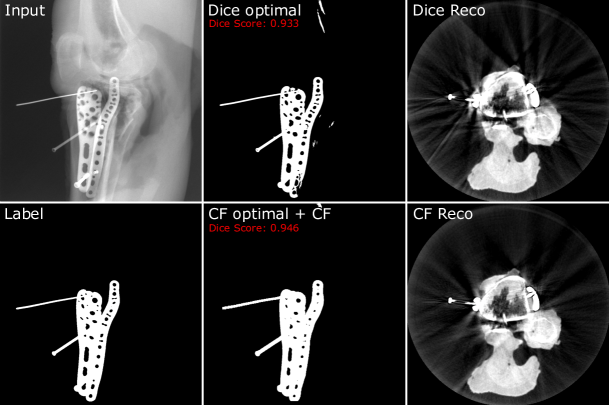

accounts for the decreasing number of possible hits towards the border of the reconstruction. Assuming that all pixels, mapped by Pisubscript𝑃iP_{\text{i}}, are part of the current segmentation mask i𝑖i, the normalized voxel values VNormsubscript𝑉NormV_{\text{Norm}} lie in the range of 0 and 1. Whereas voxels with a value of 0 correspond to no contribution of none of the segmentation masks, voxels with a value of 1 correspond to a contribution from every segmentation mask. As a consequence, the voxel values intrinsically hold information about how consistently the respective part of the metal object was segmented throughout the set of given projections. Thus, applying a threshold of e.g. 0.96 to binarize the normalized hit-counter volume to a intermediate 3D metal mask, is equivalent to including only those parts into the 3D metal mask, which were segmented in at least 96% of the projections. Further, it is important to understand that this intermediate 3D mask only describes an overestimated envelope, because we back-projected binary 2D masks without any information about the thickness of the metal at each position. When subsequently applying the final forward-projection to that binarized 3D volume, consequently only consistently segmented metal parts are included in the final set of 2D segmentation masks. As a result, inconsistencies per se and thus also false-positive segmentations are excluded and also false-negatives are included up until a certain degree. Consequently, a clean and simultaneously consistent set of segmentation masks is provided. An example of the CF’s beneficial influence on the segmentation result can be seen in Fig. 4. In the shown example, the segmentation network’s output is once binarized using a threshold that optimizes the segmentation result concerning the Dice metric and once with a threshold that is optimized for the subsequently applied CF post-processing. The CF-optimized 2D segmentation shows no false-positives and filled-up false-negatives. Furthermore, the post-processed masks achieve the higher Dice score, although not being optimized for that metric. Moreover, the corresponding reconstructions show a higher amount of streak artifacts in the case of the Dice-optimal segmentation, which are mainly due to inconsistencies withing the set of segmentation.

Refer to caption

Figure 4: Resulting segmentation masks for a given Input projection. Whereas Label shows the GT segmentation, Dice optimal shows the network’s binarized segmantation using a dice-optimal threshold, CF optimal + CF shows the segmentation result after applying the Consitency Filter with an input segmentation using a CF-optimal threshold for binarization. Further, Dice Reco and CF Reco show the corresponding reconstructions. It can be seen, that in the case of the Dice-optimal reconstruction (thus not applying the CF post-processing), the lack of consistency and the false-positive segmentation lead to heavier streak artifacts. Additionally, the segmentation mask after applying the CF using a CF-optimal threshold achieves the higher Dice score.